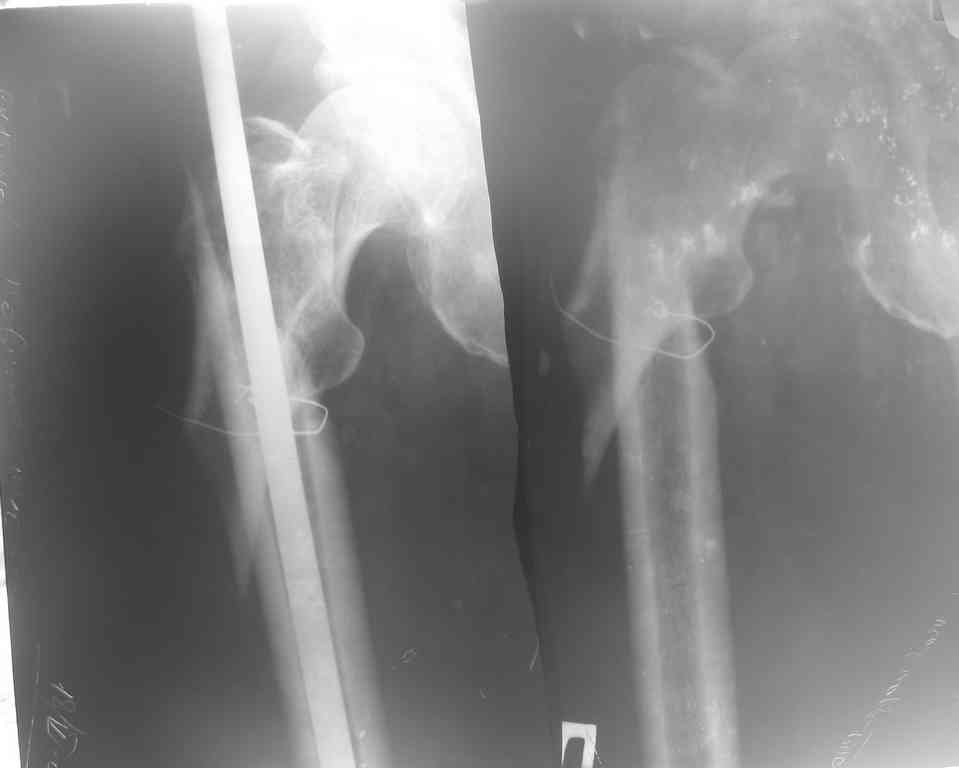

Несросщийся подвертельный перелом бедра

Глубокоуважаемые коллеги! Обратился больной 66 лет. Семь месяцев назад произведен неудачный интрамедуллярный остеосинтез штифтом Кюнчера в одном районе.

Через месяц штифт удалён, перелом несросся. Тактика лечения?